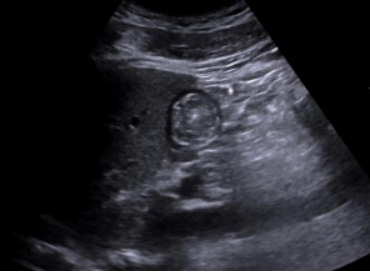

4. 标准图像应以探查到肝左叶和腹主动脉夹角处的环状结构(置于屏幕中心线), 深度以显示腹主动脉最浅深度为准(2)

图片

2  胃窦短轴标准切面超声图像